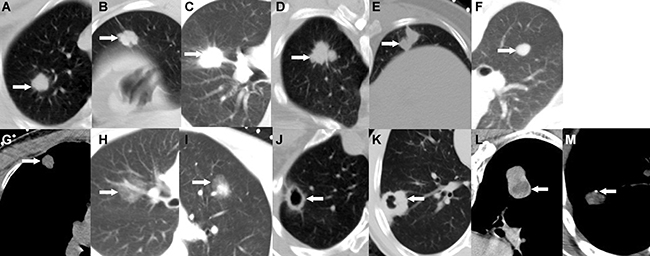

These reports included clinical data regarding sex, age, chief complaints, cigarette smoking status, previous medical histories and family histories (i.e., extra-thoracic disease history; chronic lung disease history, except cancer history; and cancer history, except lung cancer history), and histopathology. Information regarding the following chest radiological data was collected for all patients: nodule size (average of the maximum length and width) [8, 9], edge characteristics (i.e., whether the edges featured spiculated protuberances, lobulation alone, spiculation alone, or lobulation and spiculation; and whether the edges were irregular or smooth) [6], density characteristics (i.e., whether the nodules were solid, purely ground-glass, or partly solid; whether the nodules featured thin cavitations or thickened cavitations; and whether the nodules displayed necrosis and calcification) (Figure 4) and location (i.e., whether the nodules were located in the upper, middle or lower lobe). We obtained approval from our institution to use patient medical records for this study, and patient confidentiality was maintained.

Figure 4: SPN edge and density characteristics. (A) Spiculate protuberance, (B) Lobulation, (C) Spiculation, (D) Lobulation combined with spiculation, (E) Irregular edges, (F) Smooth edges, (G) Solid density, (H) Purely ground-glass, (I) Partly solid, (J) Thin cavitation, (K) Thickened cavitation, (L) Necrosis, (M) Calcification.